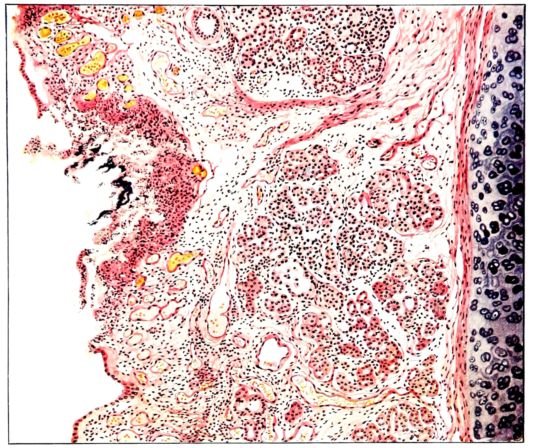

23The fluid of the pleural cavities varies volumetrically as described in the preceding section. It is, however, usually not a clear fluid, but varies from a slightly turbid, blood-stained material to a typical purulent exudate. The cloudiness may be associated with minute flecks of suspended material, but in no instance has this fluid been of the thick inspissated type which formerly would have been designated as empyema.[8] (This is mentioned with the knowledge that the term empyema is being applied now to less viscid, purulent, pleural exudates). The turgidity of the mediastinal tissue also persists, but it is very rare indeed to find anything more than a small amount of clear fluid in the pericardial sac. Only once was there a typical, fibrinous pericarditis with effusion, and this occurred where a most extensive pleural exudate was also present.[9] Where such complications have been described in serous membranes, the bronchial lymph glands, particularly at the hilum of the lung, are more involved and show, not only an increase in size and a red color on cross section, but frequently also focal areas of necrosis at the periphery, which appear as yellow patches and subsequently undergo suppurative disintegration (2, 47).

The lung remains increased in volume and its surface is mottled with vivid colors. Often these are an indication of deeper parenchymatous change. The pale pink zones, through the pleural surface of which distended alveoli are discernible, are still prominent in the upper lobe, around the margins, and on the anterior surface of the lung. The darker purple, slightly elevated, often circumscribed, infarct-like areas (25, 34, 108) may occur anywhere, but are more frequent in the lower lobes. Small, maroon, slightly depressed areas of atelectasis may also involve the borders of the lung, usually the posterior borders; or they may occur between larger and more elevated areas on either lobe. Besides the purple, firm, projecting foci, paler pink or grey nodules of similar consistence may be present and show no structure when viewed through the pleura. The distribution of the different types of change is variable, and, aside from the fact that they involve the middle and lower lobes more frequently than the upper, no general statement is possible. In a few instances, one lobe, almost always the lower, may be more voluminous than the others, and although its pleura often suggests lobular involvement, the masses tend to be confluent and suggest a pseudolobar change. Sometimes, though rarely, this approaches a true lobar type of consolidation. (Compare Figs. XIII and XXVII.) Occasionally, the changes in the lung, except its increase in size, are obscured by pleural exudate which may form a thick, buttery, rather sticky mass on the surface (12, 19, 157) (Fig. XXXVII). Such pleural exudates are rare, and likewise it is uncommon to find so little pleural granulation as in the previous group. The roughening, as a rule, is not uniform, but is more prominent over the lower lobes and in the interlobar spaces than elsewhere. It may occur when there is no definite increase in the fluid content of the pleural sac.

The lung, now sectioned, presents a surface in accord with the changes suggested from the description of its external appearance. As compared with the first stage the amount of syrupy, blood-stained exudate may be definitely decreased, especially in the upper lobe or in those portions of the lung where the solidification is less marked. Its character, too, may be more cloudy, and more ropy, or viscid; it bathes the surface and is scraped off in abundance with the blade of a knife from the underlying consolidated foci (108, 156). The bronchi and bronchioles, however, may be prominent, irrespective of the change in the parenchyma itself. From their lumina, thick, yellow pus wells forth and their mucous membrane is intensely congested. Where such involvement occurs in unconsolidated portions of the 24lung, the bronchioles are even more striking than in the hepatized areas in which the more widespread changes obscure the process. The dilatation of the bronchioles, especially in their smaller ramifications, is still conspicuous.

The consolidated areas vary greatly in size and number;[10] often they are small and involve only single lobules, which now stand out as granular, generally elevated patches on the surrounding congested plane. Their color, as on the pleura, varies. They may be dark, almost hemorrhagic, fading through the reds, pinks, and greys. They may be firm, or, at the other extreme, honeycombed by small, often narrow, cavities, from which a material similar to that described on the surface wells forth. The latter change is more frequent if the consolidated area is large. It has occurred most often in the pseudolobar and in the lobar types of the process. The pseudolobar change is differentiated, not only by the confluence of more or less definite lobular patches and by its involvement of portions of contiguous lobes rather than a single lobe, but also by variations in the color and consistence of the different lobular foci. This is in contrast with lobar involvement where the entire lobe is affected by a uniform process usually at the same stage of development. Although the consistence may vary in different portions, usually the same color is present throughout. (Compare Figs. XIV and XXVIII.) In one instance where a solid, yellow lobe was found, its center contained an irregular, fresh blood clot (Fig. XVIII), which would be sufficient to differentiate this type of consolidation from that of respiratory disease in which the initial lesion is less destructive. Sometimes the softening in a hepatized lobule or group of lobules is much more evident, and the zone becomes divided by irregular channels filled with viscid, grey or brown material (108, 149, 162). When such a condition lies just beneath the pleural surface, it may be distinctly seen from without (Fig. XXXIII). The pleura bulges, the normal topography of the local zone is lost, and it appears as a dull, somewhat projecting, circumscribed patch, two or three or more centimeters in diameter, the surface of which has a more or less characteristic brown or brownish black opacity. As soon as this is sectioned there pours from the cavity the liquefied exudate in which the destroyed pulmonary parenchyma is mixed (Fig. XXXIV). Occasionally, strands of tissue still traverse the cavity, but, as a rule, it empties itself completely, and leaves a brownish black wall. The delicate, sweet but persistent and penetrating odor is not so marked as with typical gangrene.